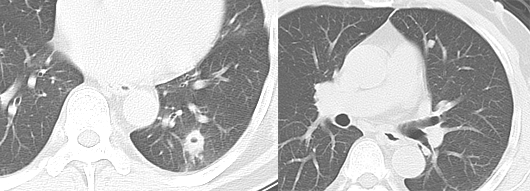

粟粒性转移

粟粒状病灶多见于甲状腺癌、肝癌、胰腺癌及绒毛膜上皮癌转移。常同时伴有纵隔淋巴结肿大及其他脏器转移。

图片

男性,45 岁。左肺上叶肺癌伴双肺粟粒性转移。